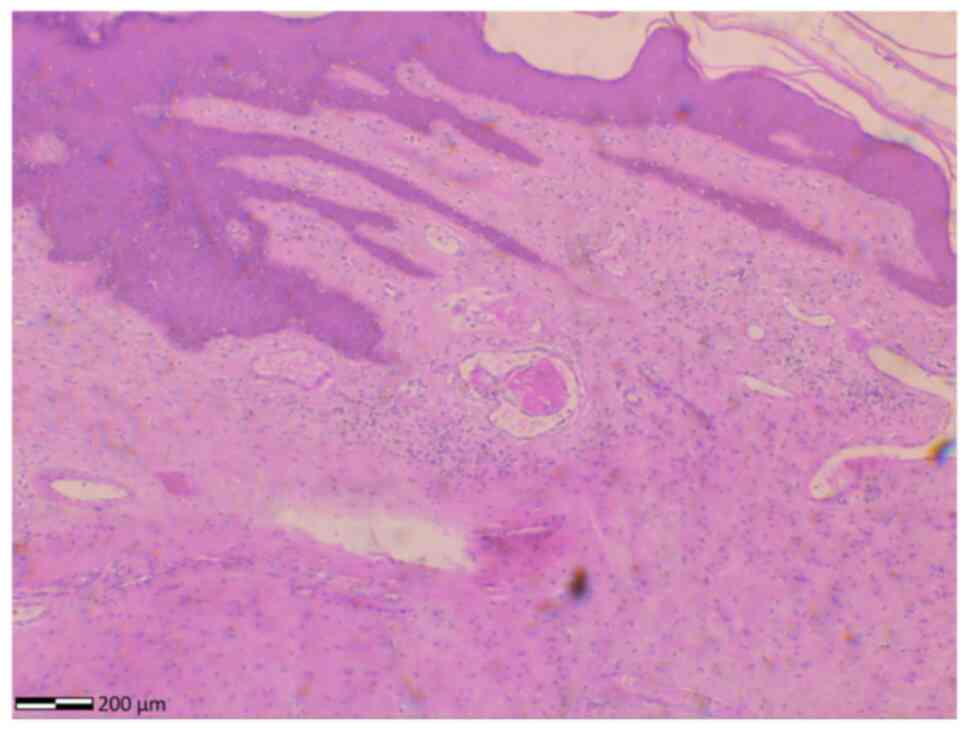

Ulcerative fibroepithetial stromal polyp of the vulva with strong clinical suspicion for vulvar malignancy: A case report and mini‑review of the literature

Fibroepithelial stromal polyps of the vulva are rare clinical entities, typically appearing as isolated polypoid stromal lesions, covered by squamous epithelium. The presence of non‑traumatic ulcerative lesions on the tumor surface, particularly when the tumor is relatively small, necessitates the differentiation from malignant lesions of the vulva. The present study describes the case of a 44‑year‑old patient who presented to an outpatient gynecological clinic, reporting as her sole symptom the presence of a mass in the vulval region, which had been increasing in size over the past 12 months. Upon examination and palpation of the external genitalia, a painless pedunculated tumor measuring ~5 cm, originating from the upper third of the right labium majus, covered with normal skin, but bearing ulcerative lesions, was found. An ulcerative fibroepithelial polyp of the vulva was suspected, and surgical treatment with wide excision of the lesion was decided upon. A histological examination of the surgical specimen confirmed the diagnosis. The immunohistochemical analysis of the tumor ruled out malignancy. Following an uneventful post‑operative course, the patient was discharged from the clinic the following day. At 6 months post‑operatively, no recurrence of the fibroepithelial polyp was found at the site of pedicle resection. The present study, also provides a brief literature review of this rare disease entity following the case presentation, highlighting the necessity of wide surgical excision of vulvar fibroepithelial polyps and their differentiation from vulvar malignancies.

Figure 1

Figure 2

Figure 3